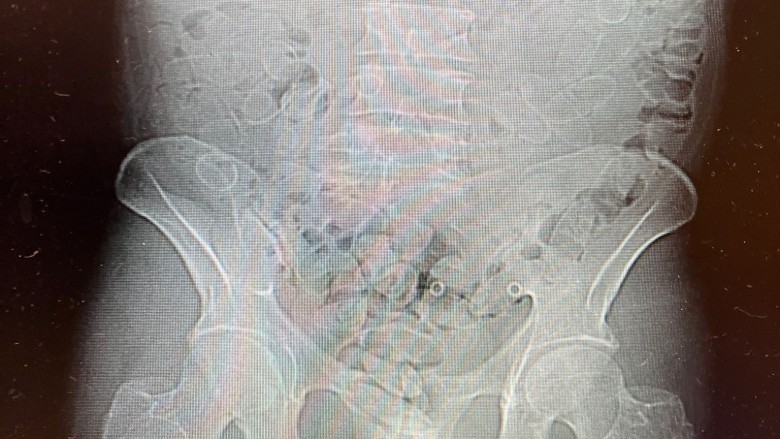

Na tym jednak sprawa się nie skończyła. Funkcjonariusze zwrócili uwagę na nerwowe zachowanie podróżnego, które mogło wskazywać, że przewozi narkotyki również wewnątrz organizmu. 40-latek przyznał później, że połknął 88 kolejnych kapsułek z kokainą. Został przewieziony do szpitala, gdzie wykonano badanie tomografem komputerowym. Wynik potwierdził obecność narkotyków w jego ciele.

Badania laboratoryjne wykazały, że w sumie w 89 kapsułkach znajdowało się prawie 0,8 kg kokainy. To ilość, której czarnorynkowa wartość oszacowano na blisko 300 tys. zł. Sprawa została potraktowana jako próba przemytu znacznej ilości narkotyków.